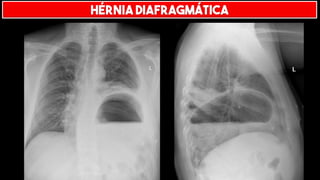

HÉRNIA DIAFRAGMÁTICA